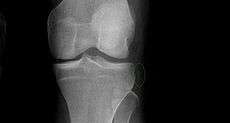

Segond fracture of left knee

Segond and reverse Segond fractures are characterized by a small avulsion,[5] or "chip", fragment of characteristic size that is best seen on plain radiography in the anterior-posterior plane. The chip of bone may be very difficult to see on the plain x-ray exam, and may be better seen on computed tomography. MRI may be useful for visualization of the associated bone marrow edema of the underlying tibial plateau on fat- saturated T2W and STIR images, as well as the associated findings of ligamentous and/or meniscal injury.